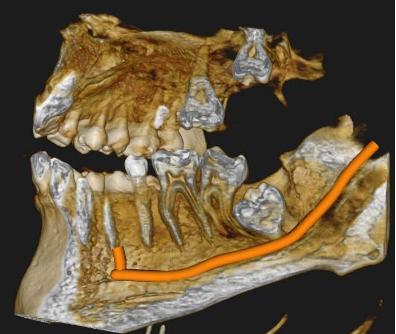

But the most powerful output was the 3D volume rendering. The CS 8200's software generated fully rotatable 3D views of both impacted teeth and their nerve canals, showing the anatomical relationship from any angle. These images did not just help the clinician plan — they transformed the patient conversation.

3D volume-rendered view showing the complex relationship between tooth 38 and the mandibular nerve canal 3D volume-rendered view showing the complex relationship between tooth 48 and the mandibular nerve canal

Fig. 4 & 5 3D volume-rendered views showing the complex anatomical relationship between the impacted wisdom teeth and their respective IAN canals. These views were used directly in the patient consultation to explain the surgical risks and secure informed consent.